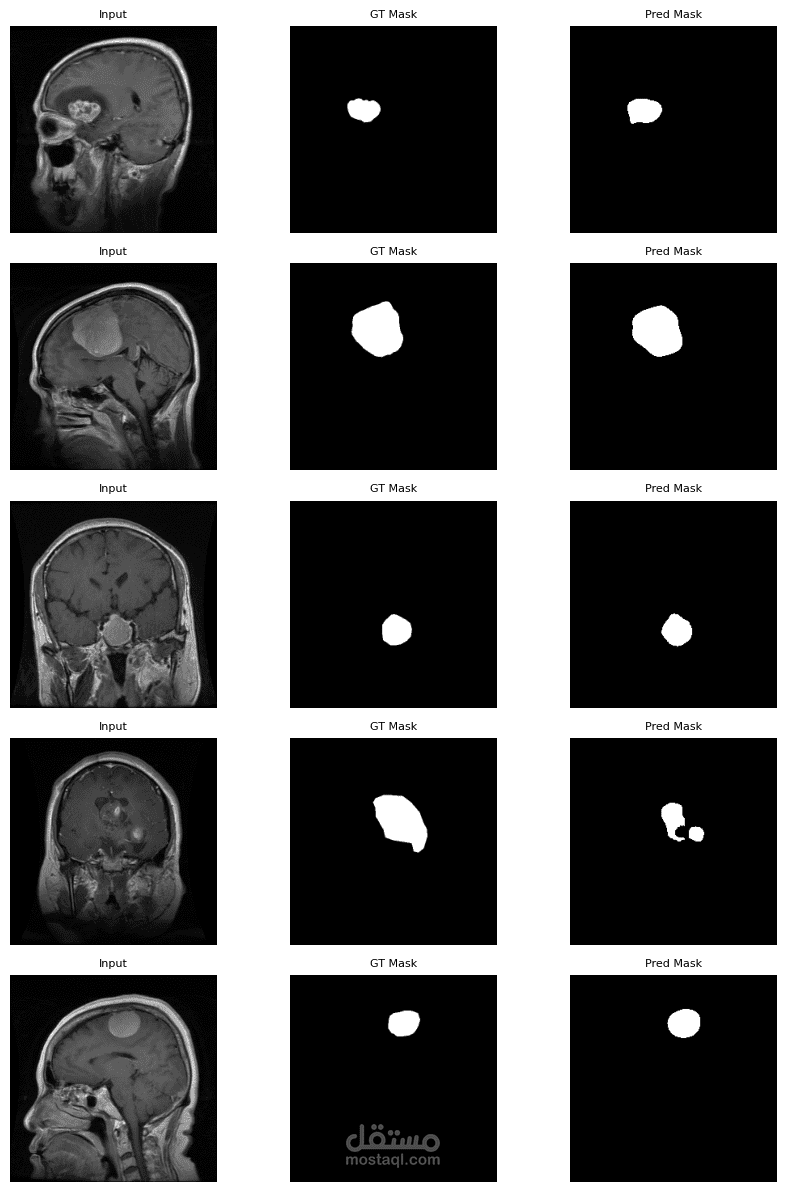

"Brain tumor segmentation using U-Net is a deep learning approach that automatically detects and outlines tumor regions in MRI scans. U-Net’s encoder–decoder architecture captures both local features and global context, making it effective for precise medical image segmentation."